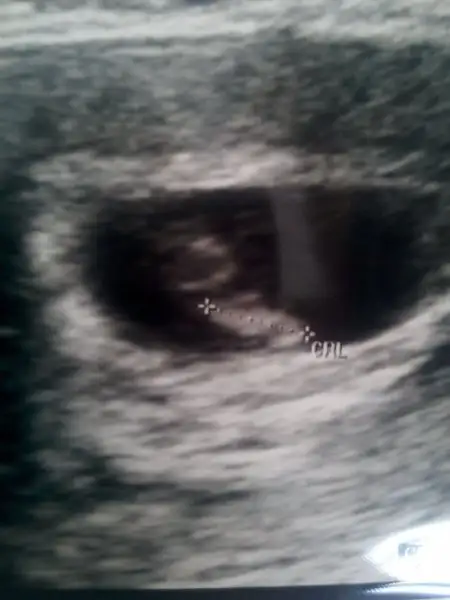

8 haftalıkken ki + mi,7 haftalıkken solda +

canım senin ilk soldan girmiş belli ewet 7 haftalıkken solda 8 ken ortaya kaymış benimkine bakarsan o da tam ortada olmuş ama ilk hep solda. seninde öyle olabilir. bu plesanta olayı nedir ben anlamadım plesanta neye deniyo ön de arkada ne demek hiç anlamadım :)